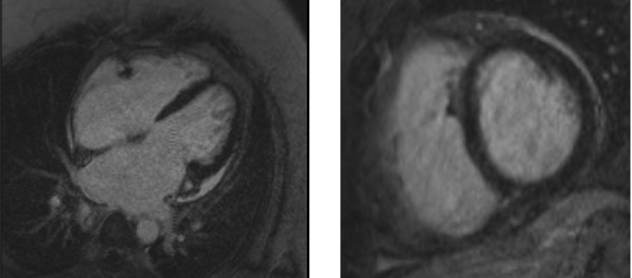

A 40-year-old male with a history of persistent Afib and AFL, unremarkable cardiac MRI on first occurrence for atrial arrhythmias, presented with dyspnea, dizziness, fatigue, and palpitations while on dofetilide. He was found to have atypical AFL with a rapid ventricular response, refractory to pharmacological and electrical cardioversion.

RCM often eludes early detection due to its presentation with preserved ejection fraction and relatively subtle heart failure symptoms. However, Afib or AFL refractory to ablation or cardioversion may serve as an early indication, especially in the context of a strong family history. We suspect progression of cardiomyopathy in this patient who, years ago, had a normal cardiac MRI. Identifying RCM through advanced imaging or genetic screening is crucial, as it enables early consideration of interventions, such as evaluation for OHT, which may prevent catastrophic outcomes. Proactive screening and repeat imaging, such as cardiac MRI, in patients with incessant atrial arrhythmias who also have a significant familial burden, can mitigate delays in treatment and improve prognosis.